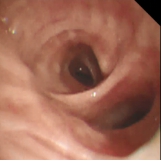

术前支气管 术中改变 术后支气管

基于以上发现,此次在上海申康医院发展中心重大临床研究项目支持下,团队进一步研究发现通过冷冻治疗设备控制,冷冻时设备将液氮输送至导管冷冻端,使冷冻端表面温度骤降,吸收环境温度,组织结冰,杀死病变组织细胞。解冻时,设备将常温氮气输送至导管冷冻端,使组织温度升高,进一步破坏病变组织细胞,达到治疗目的。

接受新疗法的患者两年前就明确诊断为慢阻肺,之后长期吸入大剂量信必可治疗,但咳痰和气急的症状仍控制不佳,本次入院复查发现肺功能明显下降,为中度阻塞性通气功能障碍。4月15日,王昌惠主任、李萍主任医师和李譞主治医师运用冷冻喷雾技术,成功完成COPD患者的支气管粘膜消融手术,术后患者无不良反应发生,第二天即顺利出院。症状得到明显改善,患者对王昌惠教授团队的感激之情溢于言表。